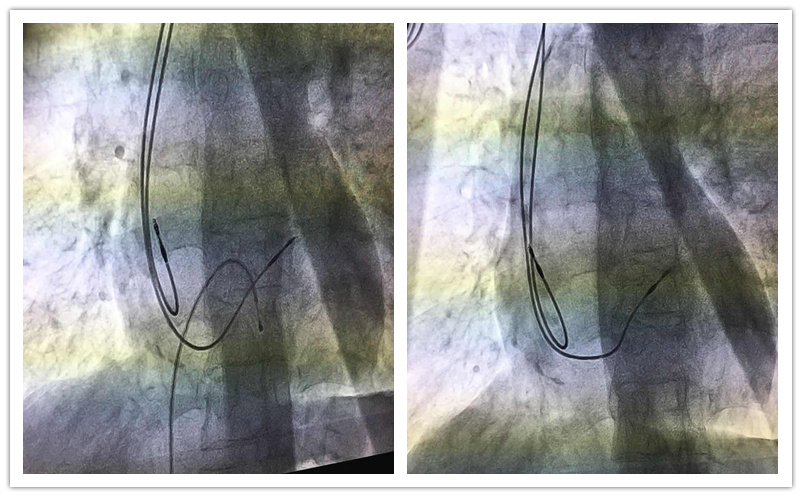

为保证患者安全、手术顺利进行,心内三科进行了术前讨论,认真分析患者的病情,并就手术细节等相关事项进行了严谨的分析和研究,制定详细周密的手术方案。医护团队默契配合、细致操作,历时1个小时,科室首例永久性人工心脏起搏器植入术顺利完成。术后,起搏器工作正常,患者感觉良好。